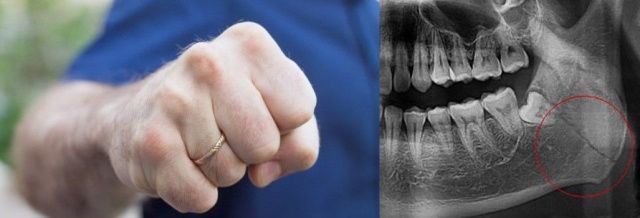

Установлено, что в январе 2022 года депутат сельского поселения, находясь в состоянии алкогольного опьянения, в ходе конфликта нанес один удар сыну в челюсть. В результате потерпевшему причинены телесные повреждения в виде закрытого перелома левого угла нижней челюсти и отека нижней челюсти.